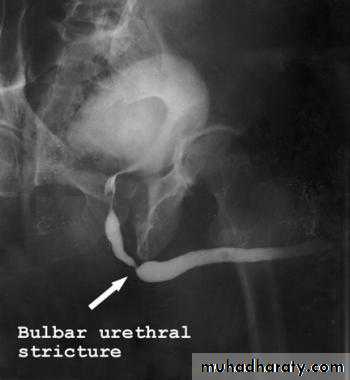

male &female reproductive tractsmammogram

genital tract and mammogram